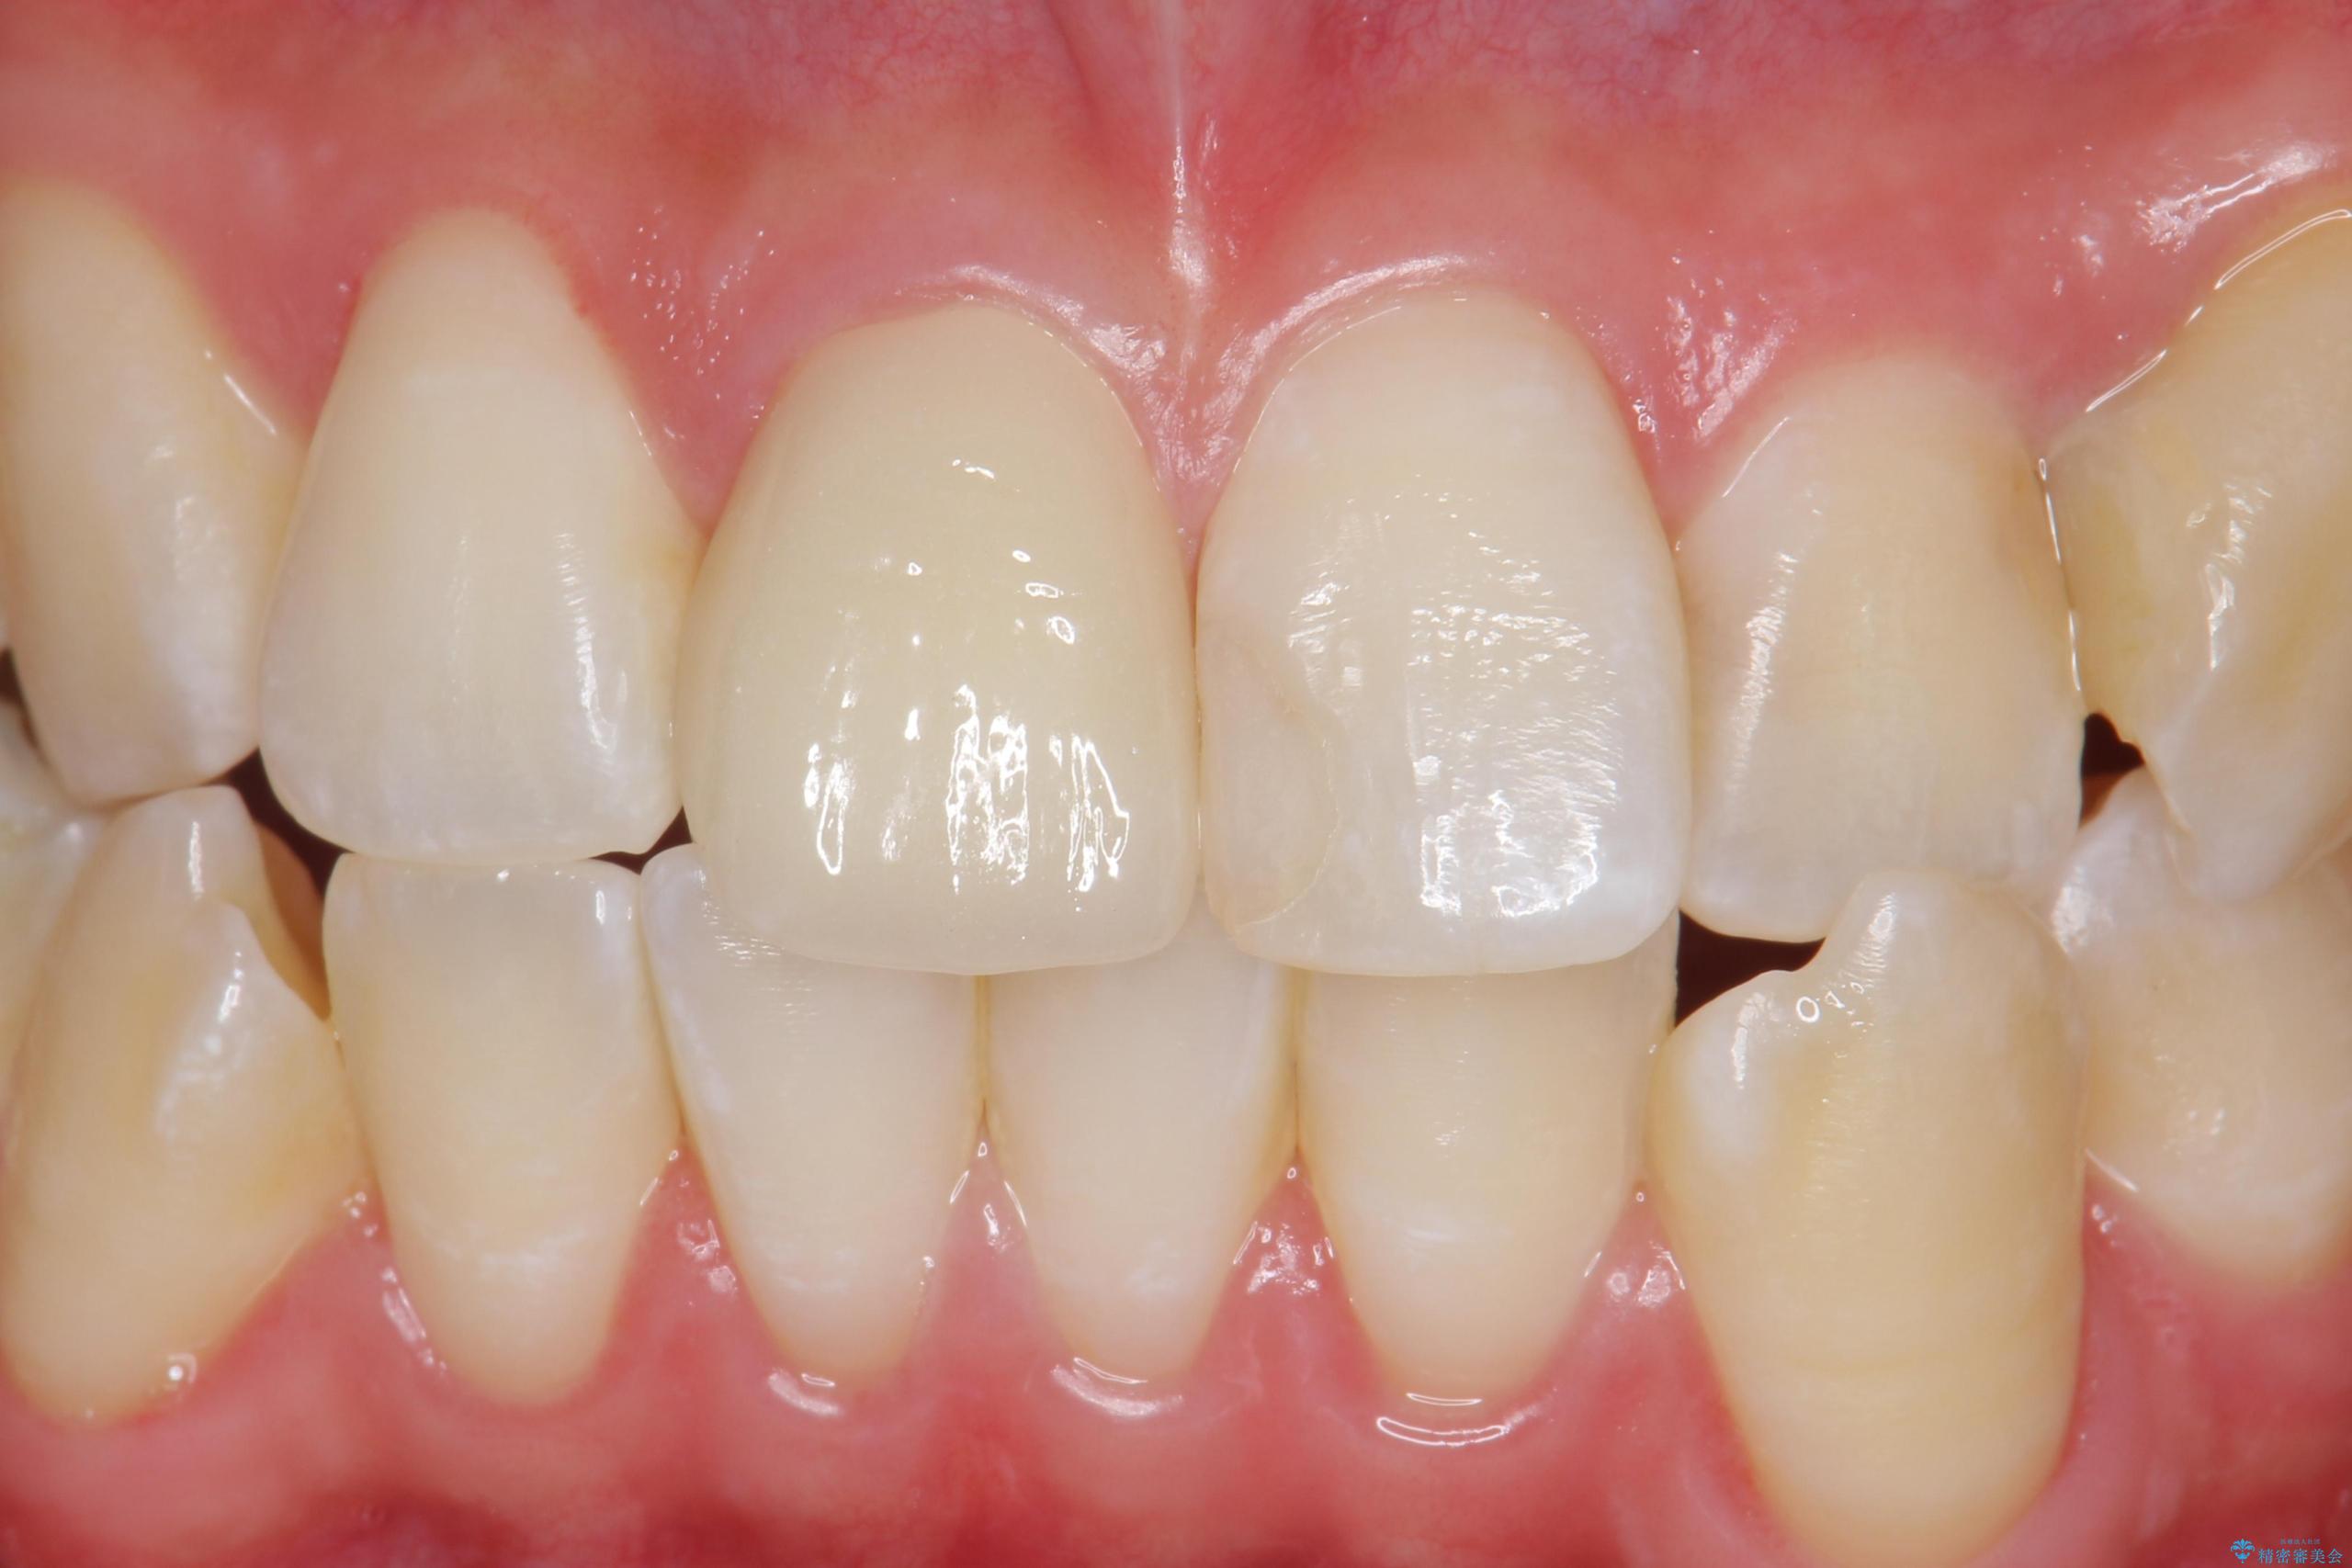

色・形ともに改善され、大変喜んでいただけました。

- 前歯のかぶせ物の色が気になるとのことで来院された患者様です。

セラミッククラウンで作り変えていきます。

- 右上1: 仮歯/11,000円、ジルコニアクラウン(スタンダード)/121,000円 合計132,000円(税込)費用は治療当時の料金となります